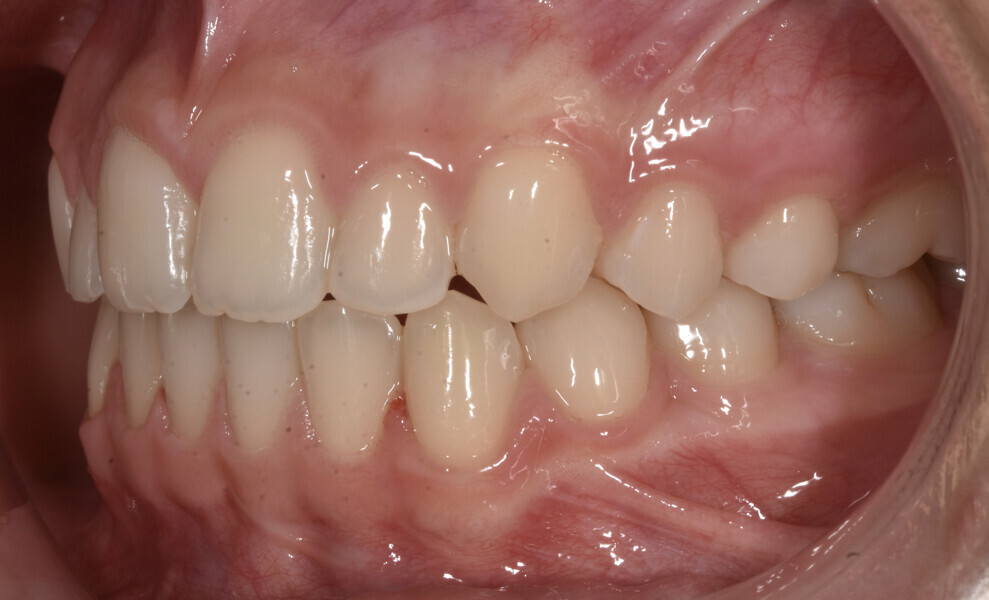

Treatment result

Final results were achieved with 42 aligners that were changed weekly (10.5 months of treatment), leading to a very aesthetic final outcome (Figs. 16–25), pleasing to the patient and her parents. All details in the anterior aesthetic zone were addressed, and it is those corrections that gave the patient the smile she desired: a smile line following the lower lip with attractive anterior buccolingual inclination and ideal gingival display according to her age.

The oblique dimension has been introduced as an important view in smile analysis,12 and it is used in this case report to support the importance of paying attention to the details (Figs. 26–28). Beauty is not a concept set in stone but a dynamic notion that evolves over time.30 Clinical assessment and patient perception should be actively correlated during orthodontic treatment planning.31 The combination of these two factors led in the presented case to excellent aesthetic results (Figs. 29–30).